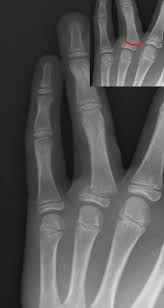

Broken Finger Finger Injuries Vary From Being A Little As Just A Bruise Or A Contusion To As Big As A Fracture Of The Bones Of The Finger Or A Dislocation Pa

Broken Finger Finger Injuries Vary From Being A Little As Just A Bruise Or A Contusion To As Big As A Fracture Of The Bones Of The Finger Or A Dislocation Pa from pics.me.me